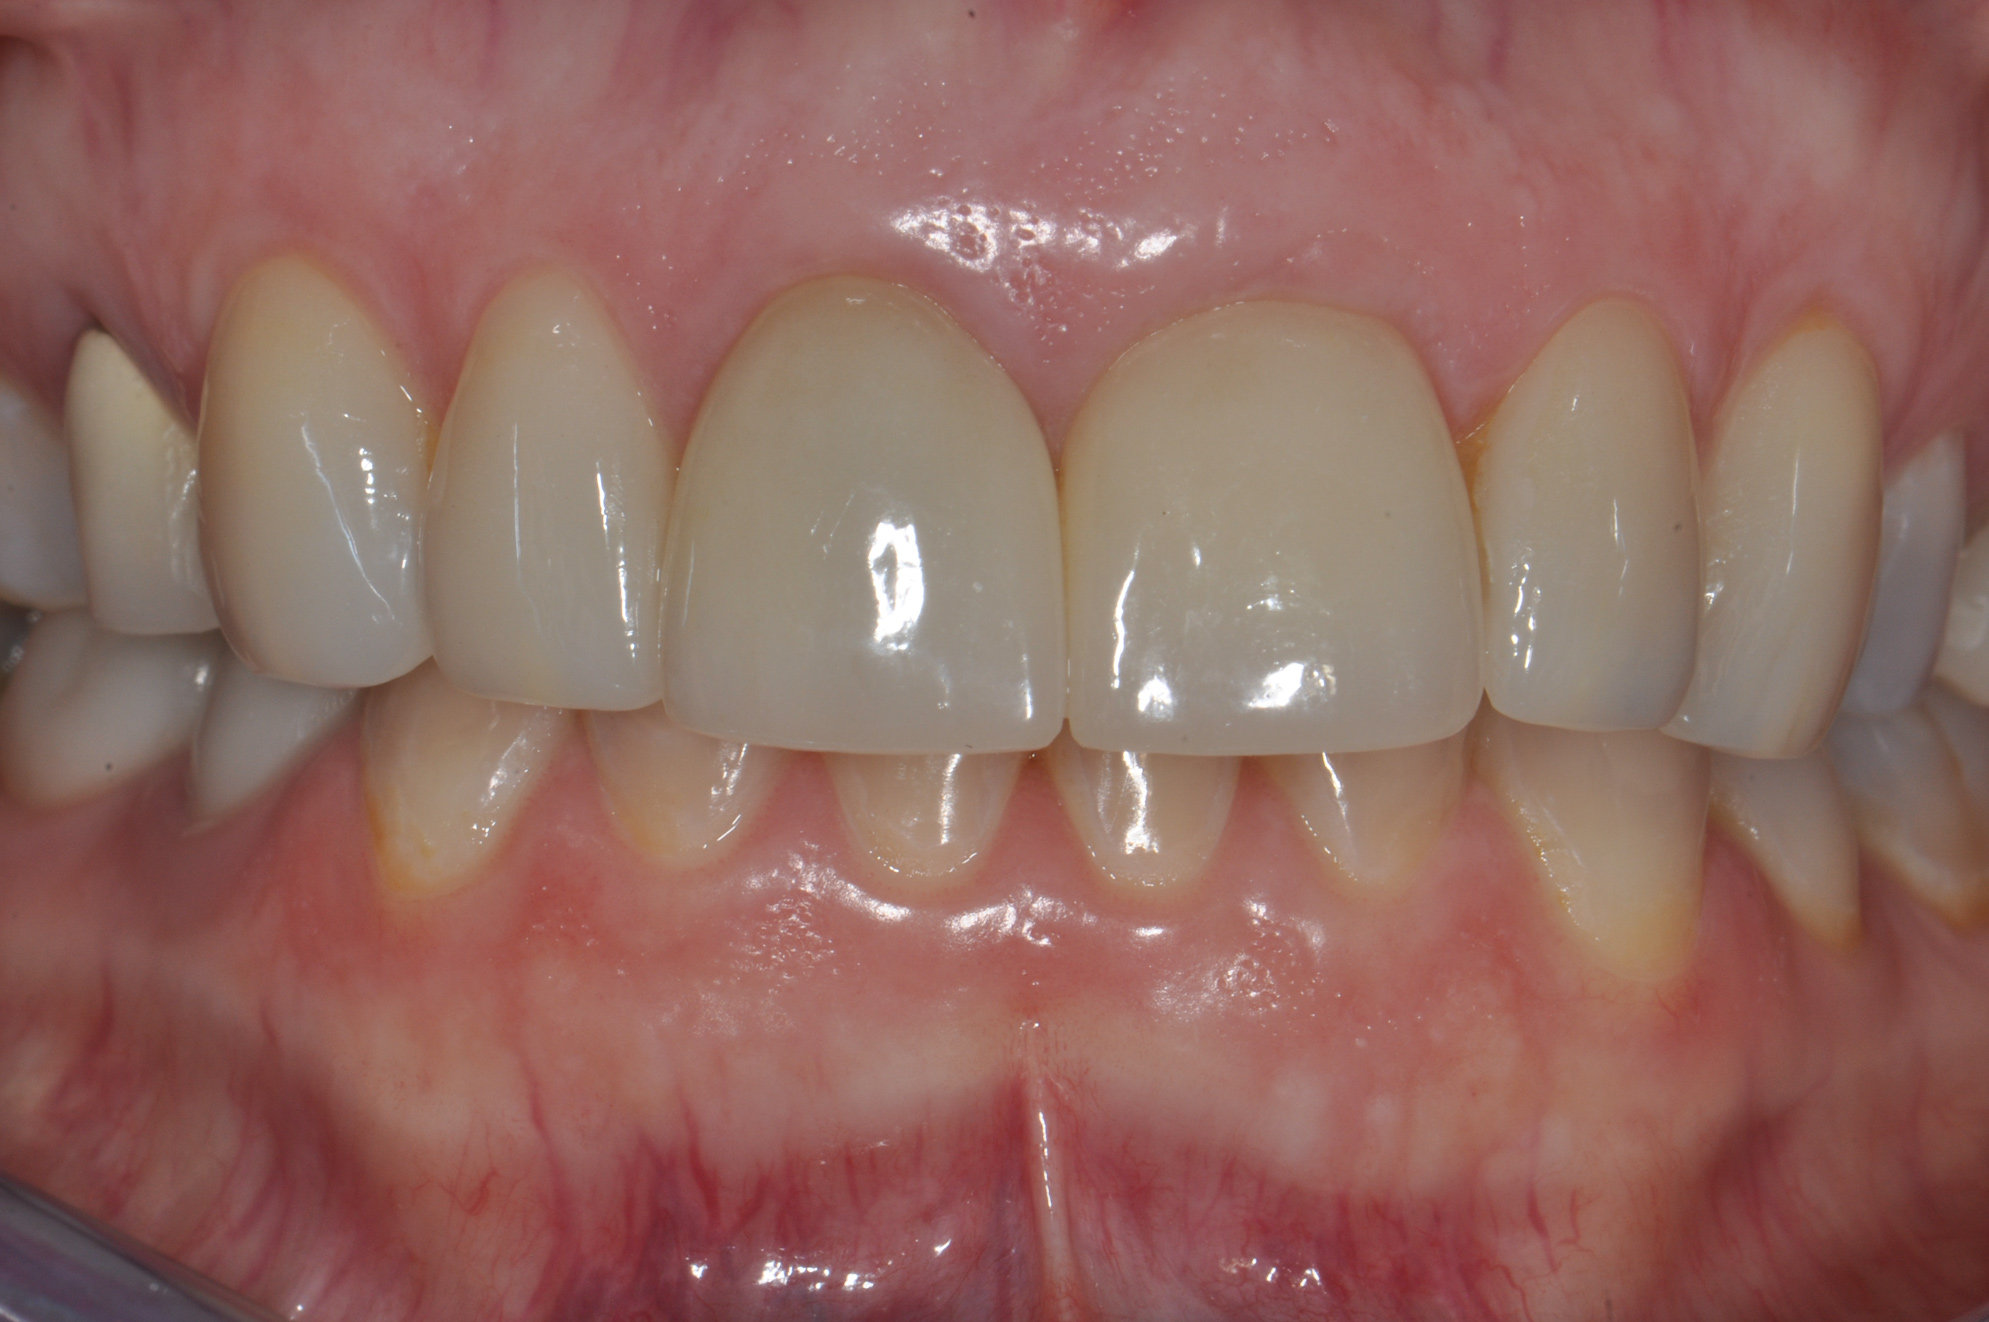

Fig 9. Completed crowns at 5 years, front view. Implant No. 9 was screw-retained (periodontist: Robert A. Levine, DDS; restorative dentist: Zola Makrauer, DMD).

Figure 9

Figure 8 shows the provisionalization of No. 8 at 6 weeks postoperatively and a screw-retained provisional restoration on No. 9 to develop the subgingival transitional zone (key Nos. 8 through 10). The transitional zone will be duplicated using the custom impression coping technique. Figure 9 and Figure 10 depict the completed crowns at 5 years; implant No. 9 was screw-retained (key No. 10). In Figure 10 note the convex contours facial to implant No. 9 that are attributed to the connective tissue grafting as part of the surgical protocol creating biotype conversion from a thick to a thicker biotype. Figure 11 through Figure 13 show 5-year postoperative patient smile, periapical x-ray, and CBCT, respectively.